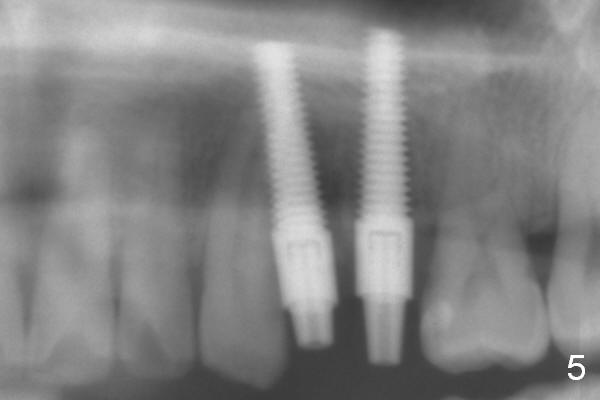

Taking 2 additional PAs with sensor 1 is frustrating (Fig.1,2), no apices shown. Osteotomy is done smoothly with 2 mm pilot drill at 20 mm, 2.5 mm reamer at 17 mm, and 3 mm reamer at 14 mm and 4.5x20 mm tap at 17 mm. The 1st intraop PA is taken with sensor 1 when 2 of 4.5x20 mm implants are placed (Fig.3); the implant at #12 is close to the root of the tooth #11. The 2nd PA is taken with sensor 2: the apex of #11 touches the implant at #12 (Fig.4). There is no separation when panoramic X-ray is taken (Fig.5). Effort is exerted to re-direct the osteotomy twice (Fig.6: tap; Fig.7: implant) without success. When the implant is removed, a PA is taken; it appears that the root of the tooth #11 has no damage (Fig.8). To obtain the best recovery, socket preservation is carried out with 50/50 cortical/cancellous allograft mixed with Osteogen (Fig.12 *) and Collagen Dressing (Fig.9: #12). A 2 (or 3)-unit provisional bridge (Fig.10: #12,13) is fabricated over the implant (Fig.9 I)/abutment (A) to cover these 2 sockets. After acid etching #11 D surface (Fig.9 >) and relining (Fig.11 *), the provisional bridge is bonded to the tooth #11 (Fig.11,12 black >) so that bone graft will be less likely dislodged.